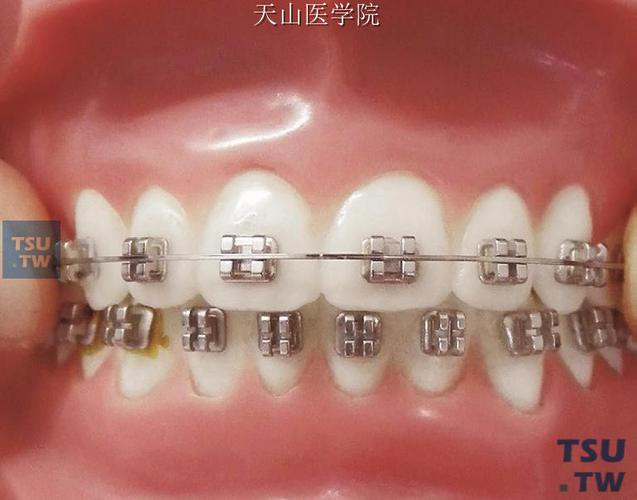

(图片来源网络,侵删)- 原因:解剖标志判断失误(如中切牙托槽粘接偏斜)、测量工具使用不当(如游标卡尺未校准)、方丝弯制时变形。

- 预防:标记前再次确认牙弓中线;定期校准测量工具;弯制弓丝时保持方丝水平,避免外力导致变形。